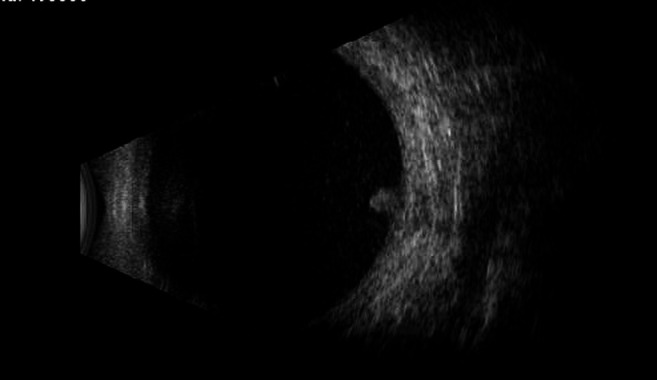

Ultrasound B scan of the left eye reveals heterogeneity of vitreous, posterior vitreous detachment and dome-shaped subretinal mass with high internal reflectivity in the region of optic nerve head shadow (figure 3).

Figure 3.

B scan of the left eye shows heterogeneity of vitreous, partial posterior vitreous detachment and oval-shaped mass with high internal reflectivity in the region of optic nerve head shadow.

The follow-up B scan of the left eye at 1 week post surgery showed increase in echoes in the vitreous cavity and the dome-shaped mass at the optic nerve head had increased diameter with high internal reflectivity (figure 4A, B). Fundus at this visit showed increase in the size of lesion at the disc margin and vitritis had increased, fundus details were obscured (figure 5).

Figure 4.

B scan of the left eye shows heterogeneity of vitreous, posterior vitreous detachment and dome-shaped subretinal mass with high internal reflectivity in the region of optic nerve head shadow, echoes have increased compared with earlier scan.